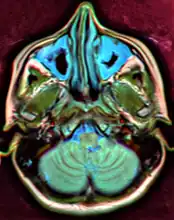

MRI image showing sinusitis. Edema and mucosal thickening appears in both maxillary sinuses. -